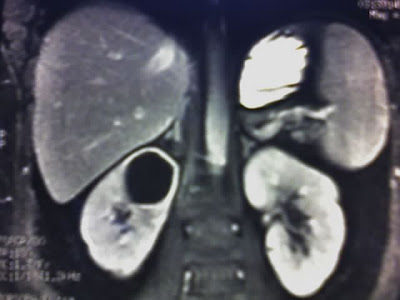

Пациенту необходимо сдать анализы крови и мочи для определения числа лейкоцитов – при абсцессе их количество увеличивается. Обязательными диагностическими процедурами являются УЗИ и компьютерная томография. Данные методики стали доступными относительно недавно, что позволило сделать результаты анализа наиболее точными и информативными для постановки диагноза.